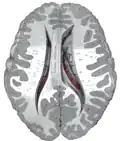

Along with the putamen, the caudate forms the dorsal striatum, which is considered a single functional structure; anatomically, it is separated by a large white-matter tract, the internal capsule, so it is sometimes also described as two structures—the medial dorsal striatum (the caudate) and the lateral dorsal striatum (the putamen). In this vein, the two are functionally distinct not because of structural differences, but merely because of the topographical distribution of function.

The caudate nuclei are near the center of the brain, sitting astride the thalamus. There is a caudate nucleus in each hemisphere of the brain. Each nucleus is C-shaped, with a wider "head" (caput in Latin) at the front, tapering to a "body" (corpus) and a "tail" (cauda). Sometimes a part of the caudate nucleus is called the "knee" (genu).[6] The caudate head receives its blood supply from the lenticulostriate artery; the tail of the caudate receives its blood supply from the anterior choroidal artery.[7]

The head and body of the caudate nucleus form part of the floor of the anterior horn of the lateral ventricle. The body travels briefly towards the back of the head; the tail then curves back toward the anterior, forming the roof of the inferior horn of the lateral ventricle. This means that a coronal section (on a plane parallel to the face) that cuts through the tail will also cross the body and head of the caudate nucleus.